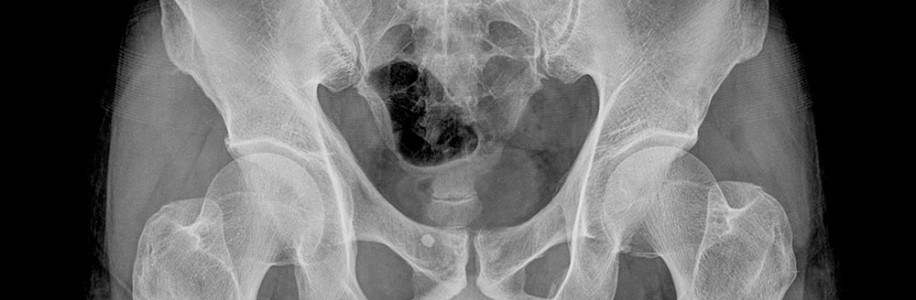

Κατάγματα κοτύλης και λεκάνης

Τα κατάγματα κοτύλης και λεκάνης έχουν συχνότητα 3-5%  όλων των καταγμάτων του ανθρωπίνου σώματος. Στους νέους ανθρώπους τα κατάγματα κοτύλης και λεκάνης είναι αποτέλεσμα της επίδρασης μεγάλων δυνάμεων στο ανθρώπινο σώμα και για αυτό αποκαλούνται υψηλής ενέργειας κακώσεις. Η αιτία των καταγμάτων κοτύλης και λεκάνης είναι κυρίως τα τροχαία ατυχήματα αλλά και τα εργατικά ατυχήματα.